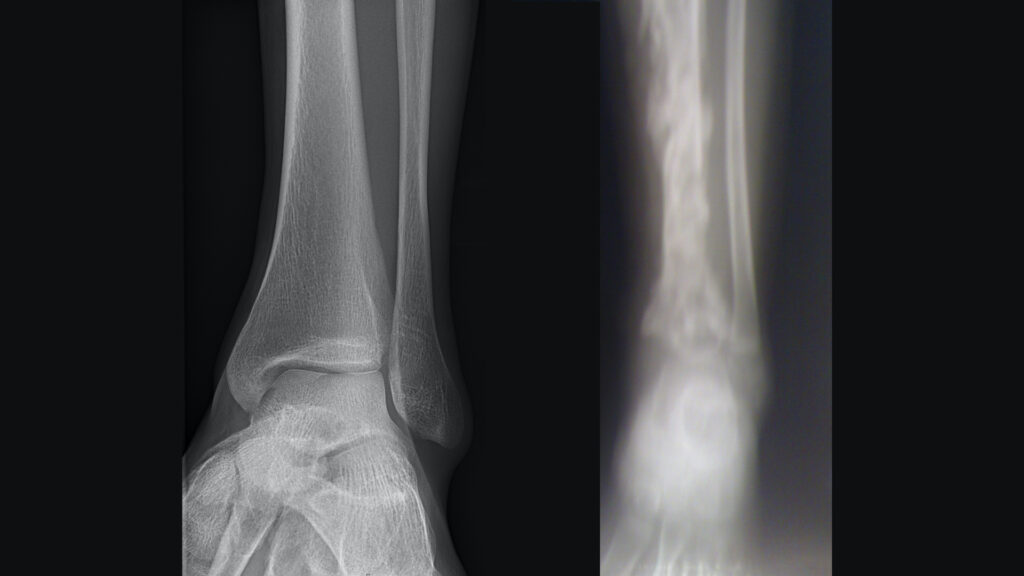

Ewing sarkomu, nadir fakat agresif bir kemik kanseri türüdür ve genellikle 10 ile 20 yaşları arasındaki gençlerde görülür. Ewing sarkomu, pelvis, uyluk kemiği veya kaburga gibi uzun kemiklerde başlar. Kondrosarkom, kıkırdak dokusunda başlayan kanser türüdür. Kıkırdak, kemikleri kaplayan yumuşak doku olup, bu kanser türü daha çok orta yaş ve ileri yaştaki bireylerde görülür.

Kemik kanseri tanısı, doktorların hastanın tıbbi geçmişini ve fiziksel muayenesini değerlendirerek konur. Röntgen, ilk değerlendirme için kullanılan yaygın bir yöntemdir. Kemiklerdeki anormal değişiklikleri gösterebilir. Daha ayrıntılı görüntüler sağlamak için MR ve bilgisayarlı tomografi (BT) taramaları kullanılabilir. Kanserin türünü ve evresini belirlemek için kanserli bölgeden hücre örnekleri alınarak laboratuvar ortamında incelenir.